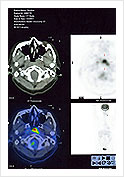

• PET scan confirmation of primary and metastalle disease